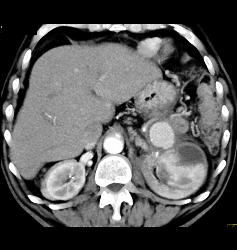

Page Kidney With Bleeding Splenic Artery Aneurysm- See Sequence